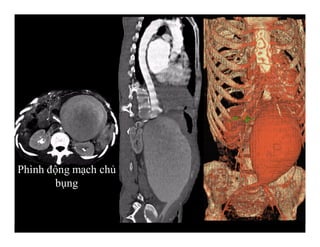

Phình động mạch chủ bụng-Hình tái tạo 3 D

Phình động mạch chủ

bụng